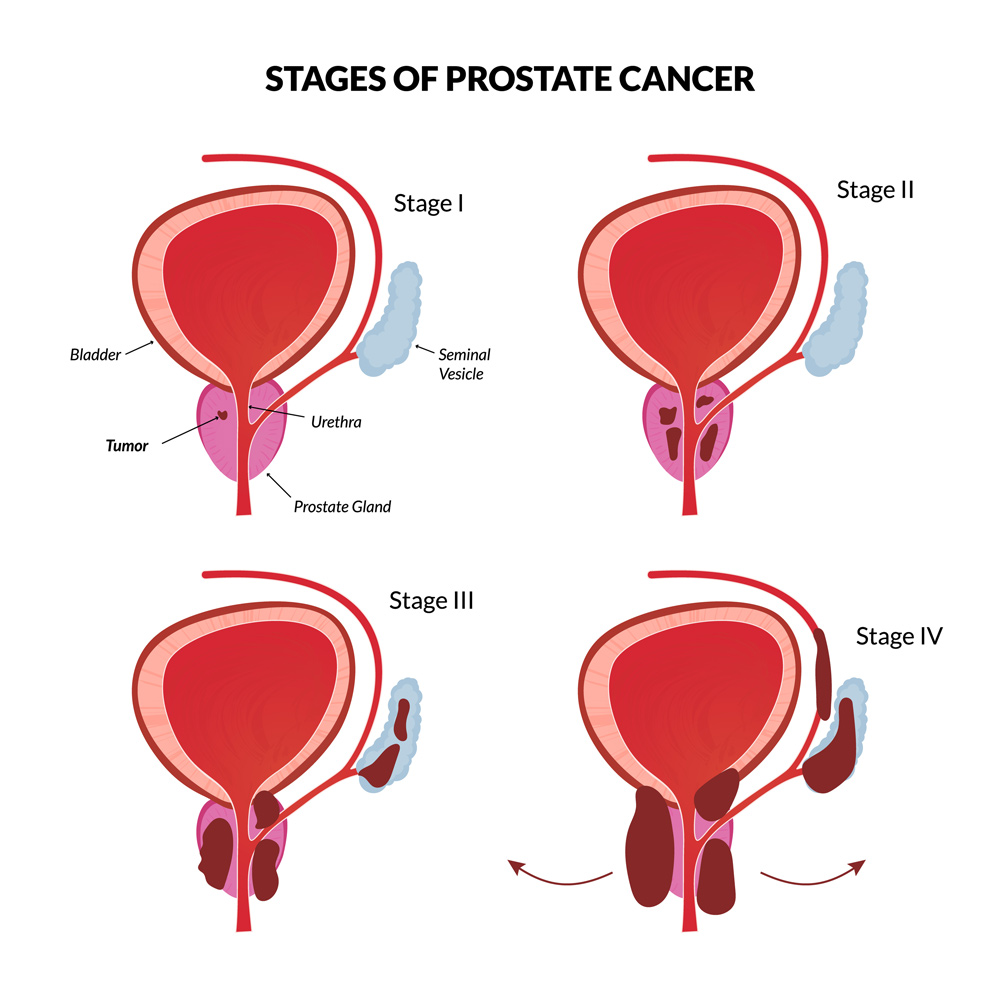

Prostate Cancer Stages – University Health News

Staging and grading | Early prostate cancer – Macmillan Cancer Support

A generalized overview of prostate cancer (PCa) progression …